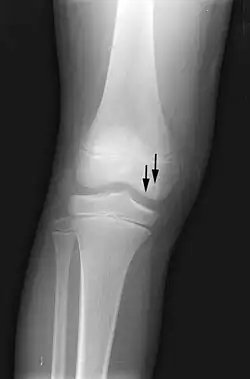

X-ray images of avascular necrosis in the early stages usually appear normal. In later stages it appears relatively more radio-opaque due to the nearby living bone becoming resorbed secondary to reactive hyperemia.[2] The necrotic bone itself does not show increased radiographic opacity, as dead bone cannot undergo bone resorption which is carried out by living osteoclasts.[2] Late radiographic signs also include a radiolucency area following the collapse of subchondral bone (crescent sign) and ringed regions of radiodensity resulting from saponification and calcification of marrow fat following medullary infarcts.

-

Radiography of total avascular necrosis of right humeral head. Woman of 81 years with diabetes of long evolution. -

Radiography of avascular necrosis of left femoral head. Man of 45 years with AIDS. -

Nuclear magnetic resonance of avascular necrosis of left femoral head. Man of 45 years with AIDS. -

The intravertebral vacuum cleft sign (at white arrow) is a sign of avascular necrosis. Avascular necrosis of a vertebral body after a vertebral compression fracture is called Kümmel's disease.[20] -

Pathology of avascular necrosis, with a photograph of a cross-section of the involved bone at top left. The reactive zone shows irregular trebaculae with empty lacunae, and fibrosis of the marrow space.